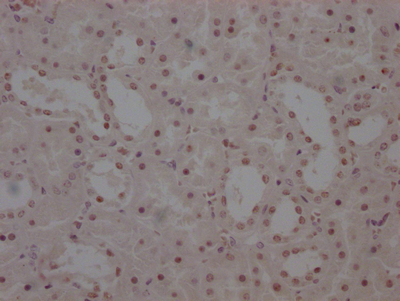

The image on the left is immunohistochemistry of paraffin-embedded Human thyroid cancer tissue using CSB-PA274333(DKK3 Antibody) at dilution 1/30, on the right is treated with fusion protein. (Original magnification: ×200)

The image on the left is immunohistochemistry of paraffin-embedded Human gastric cancer tissue using CSB-PA274333(DKK3 Antibody) at dilution 1/30, on the right is treated with fusion protein. (Original magnification: ×200)